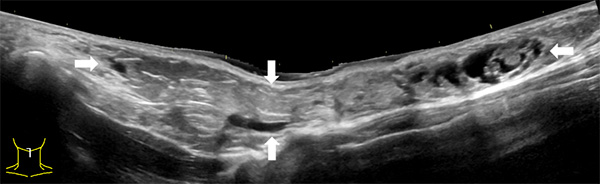

由于淋巴管畸形可发生在身体的任何部位,大多数发生在头颈部,其次为腋窝、纵膈及四肢。通常进行超声、磁共振、CT、诊断性抽液等检查,必要时依据情况进行穿刺活检,基本可以确诊。当怀疑患有淋巴管畸形时,应首先做超声检查,查清楚病变的部位、性质、大小及与周围组织的关系,评估是否需要治疗以及如何治疗。

淋巴管畸形超声:精准定位病灶部位范围以及与周边脏器的关系

超声难以确诊的病例,或病变周围结构较复杂(如在颈部、纵隔等部位)以及位置较深(如在腹腔、盆腔等部位)治疗难度大、风险高时,往往需加做磁共振检查,更精确评估病情。当影像学检查难以诊断时,也可行诊断性穿刺,若穿刺抽出淡黄色清亮淋巴液即可诊断为淋巴管畸形,若抽出陈旧性血液结合细胞学检查可诊断为淋巴管瘤伴出血。